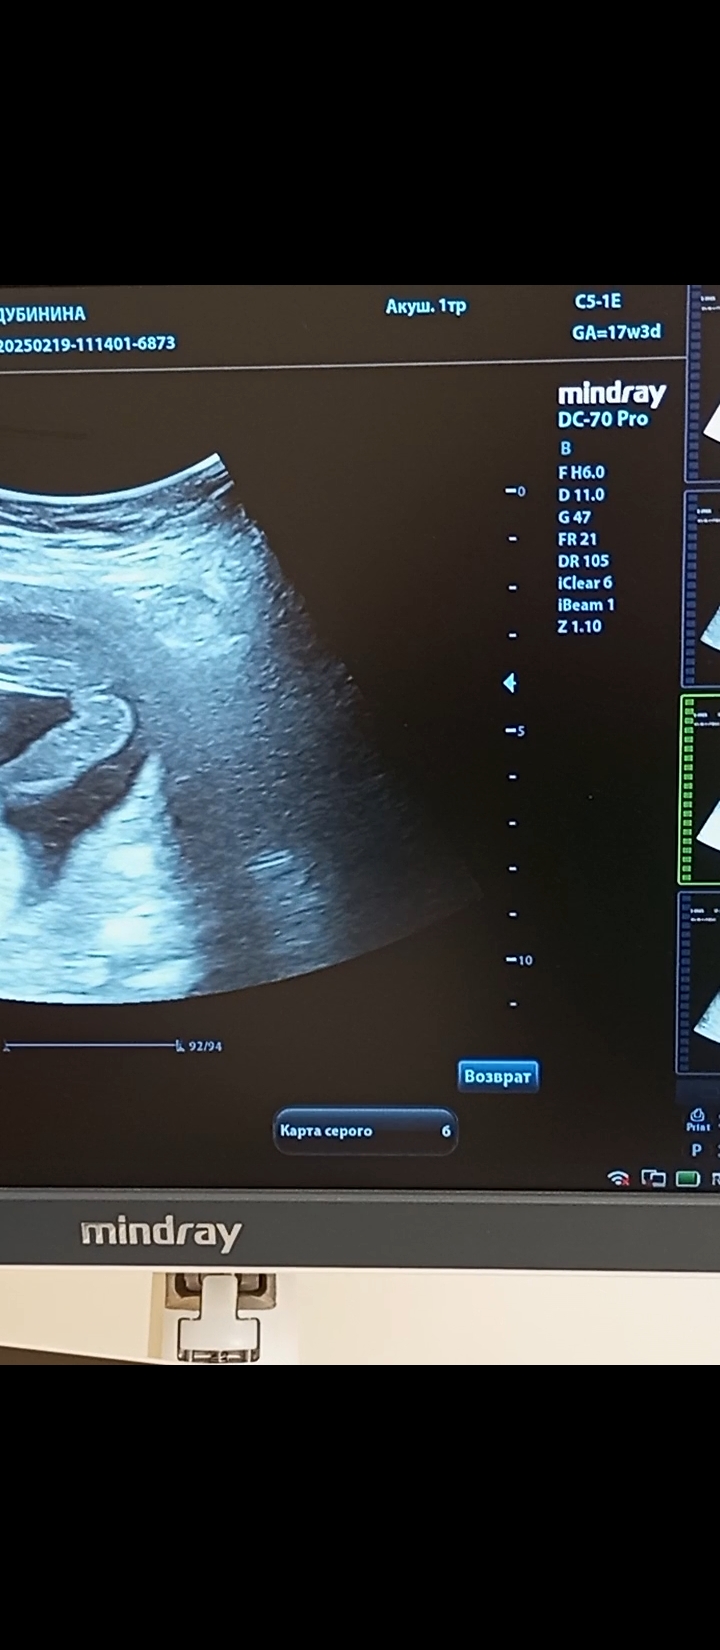

Валентина в Благополучная беременность 9 месяцев Пол мальчик или девочка? Пол малыша Девочки а здесь кого видно?)) Посмотрите еще 20 записей на эту тему Отменить Ответить Eva Девочка тут 01.03.2025 Ответить Яна Парнем чет не пахнет тут😂 27.02.2025 Ответить Татьяна Похоже на девочку 27.02.2025 Ответить Мама Лиля Девчуля 27.02.2025 Ответить Мила Девочка 27.02.2025 Ответить Людмилка Девочка🤗 27.02.2025 Ответить Camy Девочка 27.02.2025 Ответить Natalie ))))) Camy, согласна 27.02.2025 Ответить Пол 2 скрининг 20 нед Чаты Беременных Выберите чат: Январята-2026 Февралята-2026 Мартята-2026 Апрелята-2026 Майчата-2026 Июнята-2026 Июлята-2026 Августята-2026